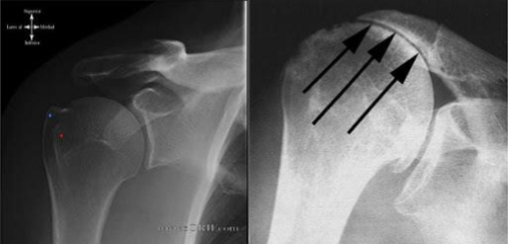

impingement

a condition where the rotator cuff tendons become irritated and inflamed due to compression during shoulder movement